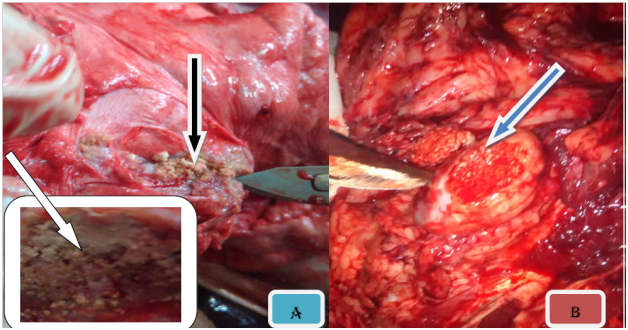

On the basis of gross pathology, in 556 slaughtered swine showed that 19.6% (109/556) were found to have tuberculous like lesions in parenchymatous organs of which 12% (69/556) were from lymph nodes, 5.7% (32/556) of the lungs, 1% (6/556) of the liver and 0.36% (2/556) of the spleen (Figure 2). The tuberculous like lesions found in lymph nodes, particularly those of mesenteric and retropharyngeal, were statistically significant (P < 0.05) than in lungs and associated lymph node. The majority of the lesions were considered to be of typical tuberculous lesions characterized by central round, oval, or irregular, often coalescing areas of caseous necrosis and calcification. The calcified lesions were exceedingly distributed in different lymph nodes and parts of the lungs (Figure 3).

Figure 3 Gross TB like lesion in different organs. Note: The typical caseuos calcified on left caudal lung (A), caseous exudates lesions in retropharyngeal lymph node (B), multifocal hepatic nodules (C), and typical caseous exudates in submandibular lymph node; after parafinized (black arrow) (D).